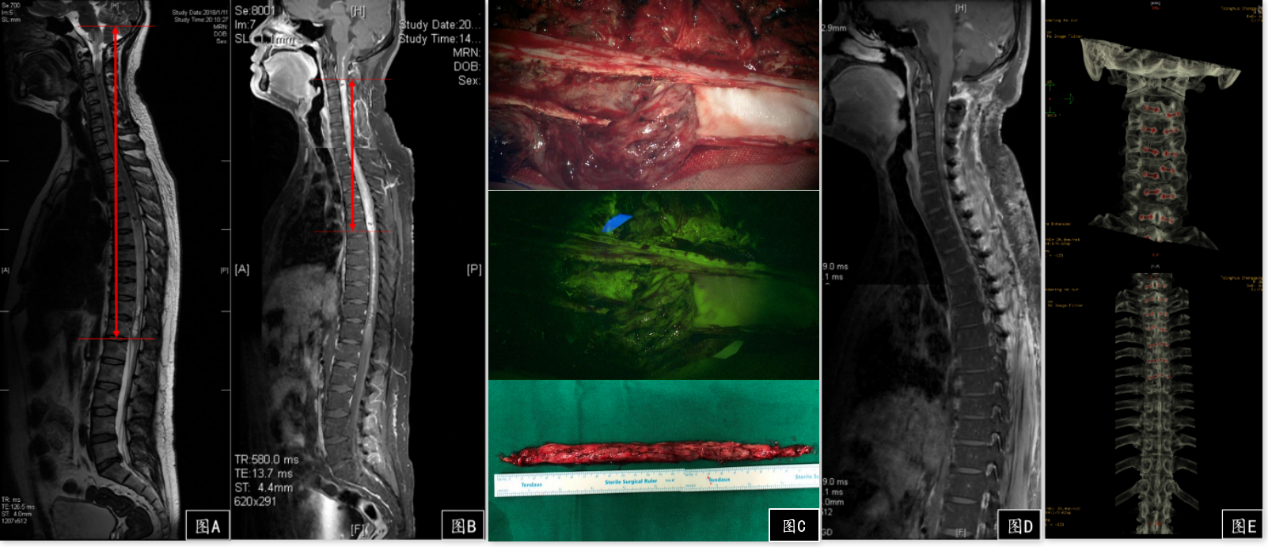

核磁共振检查报告回来后所有人都惊呆了——肿瘤实体部分上端至颈2椎体水平,下端至胸6椎体水平,两端囊变贯穿脑干和整个脊髓,全球都罕有类似病例。肿瘤巨大,术中脊髓损伤严重的话,患者很可能出现呼吸衰竭、高位截瘫等。经过充分的术前评估和准备,手术从白天到黑夜,进行了整整11个小时,王贵怀运用精湛的技术完整剖出了26cm长的脊髓髓内肿瘤,这也是目前有文章报道的最长脊髓肿瘤的世界纪录。病理确诊是室管膜瘤,这种肿瘤以躯体疼痛、麻木多见,很多病人被误诊为颈椎病,核磁共振可以协助诊断。如今阿雷已经转入康复科继续治疗,等待他的是光明的未来。

图A 磁共振T2像显示肿瘤累及脑干和全部脊髓;图B 增强扫描示肿瘤实体部分上至C2下至T6,强化明显,血供丰富;图C 荧光引导下肿瘤完整切除,长26cm;图D 术后复查核磁提示肿瘤切除满意;图E 术后CT复查提示所有椎板复位满意